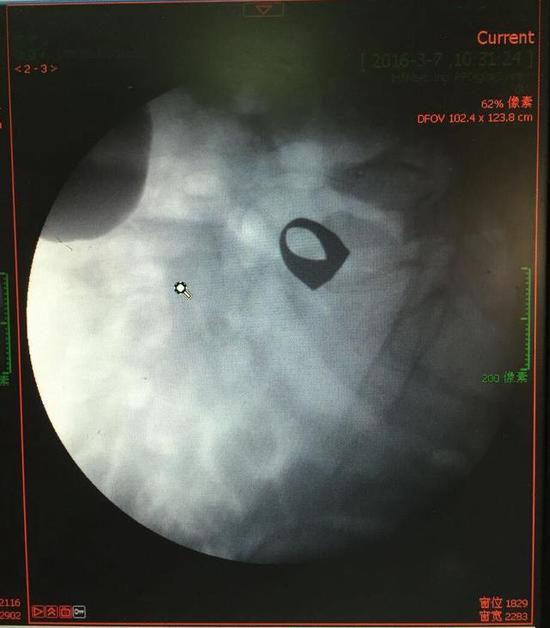

考慮到患者年齡較大,有冠心病,曾經(jīng)中過風(fēng),高血壓極高危級,遂把老人安排在帶有監(jiān)護(hù)的病房,立即給予吸氧,補液等治療。醫(yī)院立刻開啟綠色通道,醫(yī)護(hù)人員專門陪伴病人做了增強CT,腹部平片,和碘水造影,確定戒指的位置。檢查結(jié)果提示戒指位于右下腹小腸內(nèi),距回盲瓣體表投影約5cm。

3月9日,夏澤鋒教授細(xì)心的給病人做結(jié)腸鏡檢查,找到回盲瓣,調(diào)整結(jié)腸鏡鏡頭,快速的進(jìn)入小腸。結(jié)腸鏡緩緩上行至距離回盲瓣5cm的小腸,沒有戒指。繼續(xù)上行,至20cm的地方,仍然沒有找到戒指。

此時一個又一個大大的疑問出現(xiàn)在每個在場的醫(yī)護(hù)人員腦海中,戒指還在小腸里嗎?戒指在哪個位置呢?夏教授立刻聯(lián)系放射科,拍片子,發(fā)現(xiàn)戒指已經(jīng)移動了,從右側(cè)移動到了左側(cè)去了。放射科醫(yī)師建議,戒指有可能會繼續(xù)沿腸道下行,如果過了回盲瓣,就可以自行排出,免除手術(shù)痛苦。教授們采納了這個意見,立即給予促進(jìn)胃腸道動力藥,枸櫞酸莫沙必利片,每日口服三次,另外配合灌腸治療,促進(jìn)腸道蠕動,利于戒指排出。